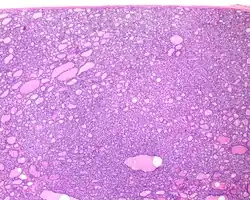

Several specific features must be identified for the tumor to be classified in this new category, while exclusion criteria should also be evaluated.

1) Encapsulated or partially encapsulated. The tumors are usually very well delimited or circumscribed, with the majority encapsulated, surrounded by a well formed fibrous connective tissue capsule.

2) Complete absence of invasion of any kind in a tumor that has been thoroughly and carefully evaluated with the whole capsule of the lesion sampled.

3) Predominantly follicular pattern of growth. Papillary structures should not be present. Further, solid, insular, or trabecular architecture must be <30% of the overall tumor for this category to still apply. Colloid (the material that thyroid follicular cells create) is easily identified throughout.

- ^ Image by Mikael Häggström, MD. Reference for findings: Rachel Jug, M.B.B.Ch., B.A.O., David Poller, M.D., Xiaoyin "Sara" Jiang, M.D. "NIFTP". Pathology Outlines.